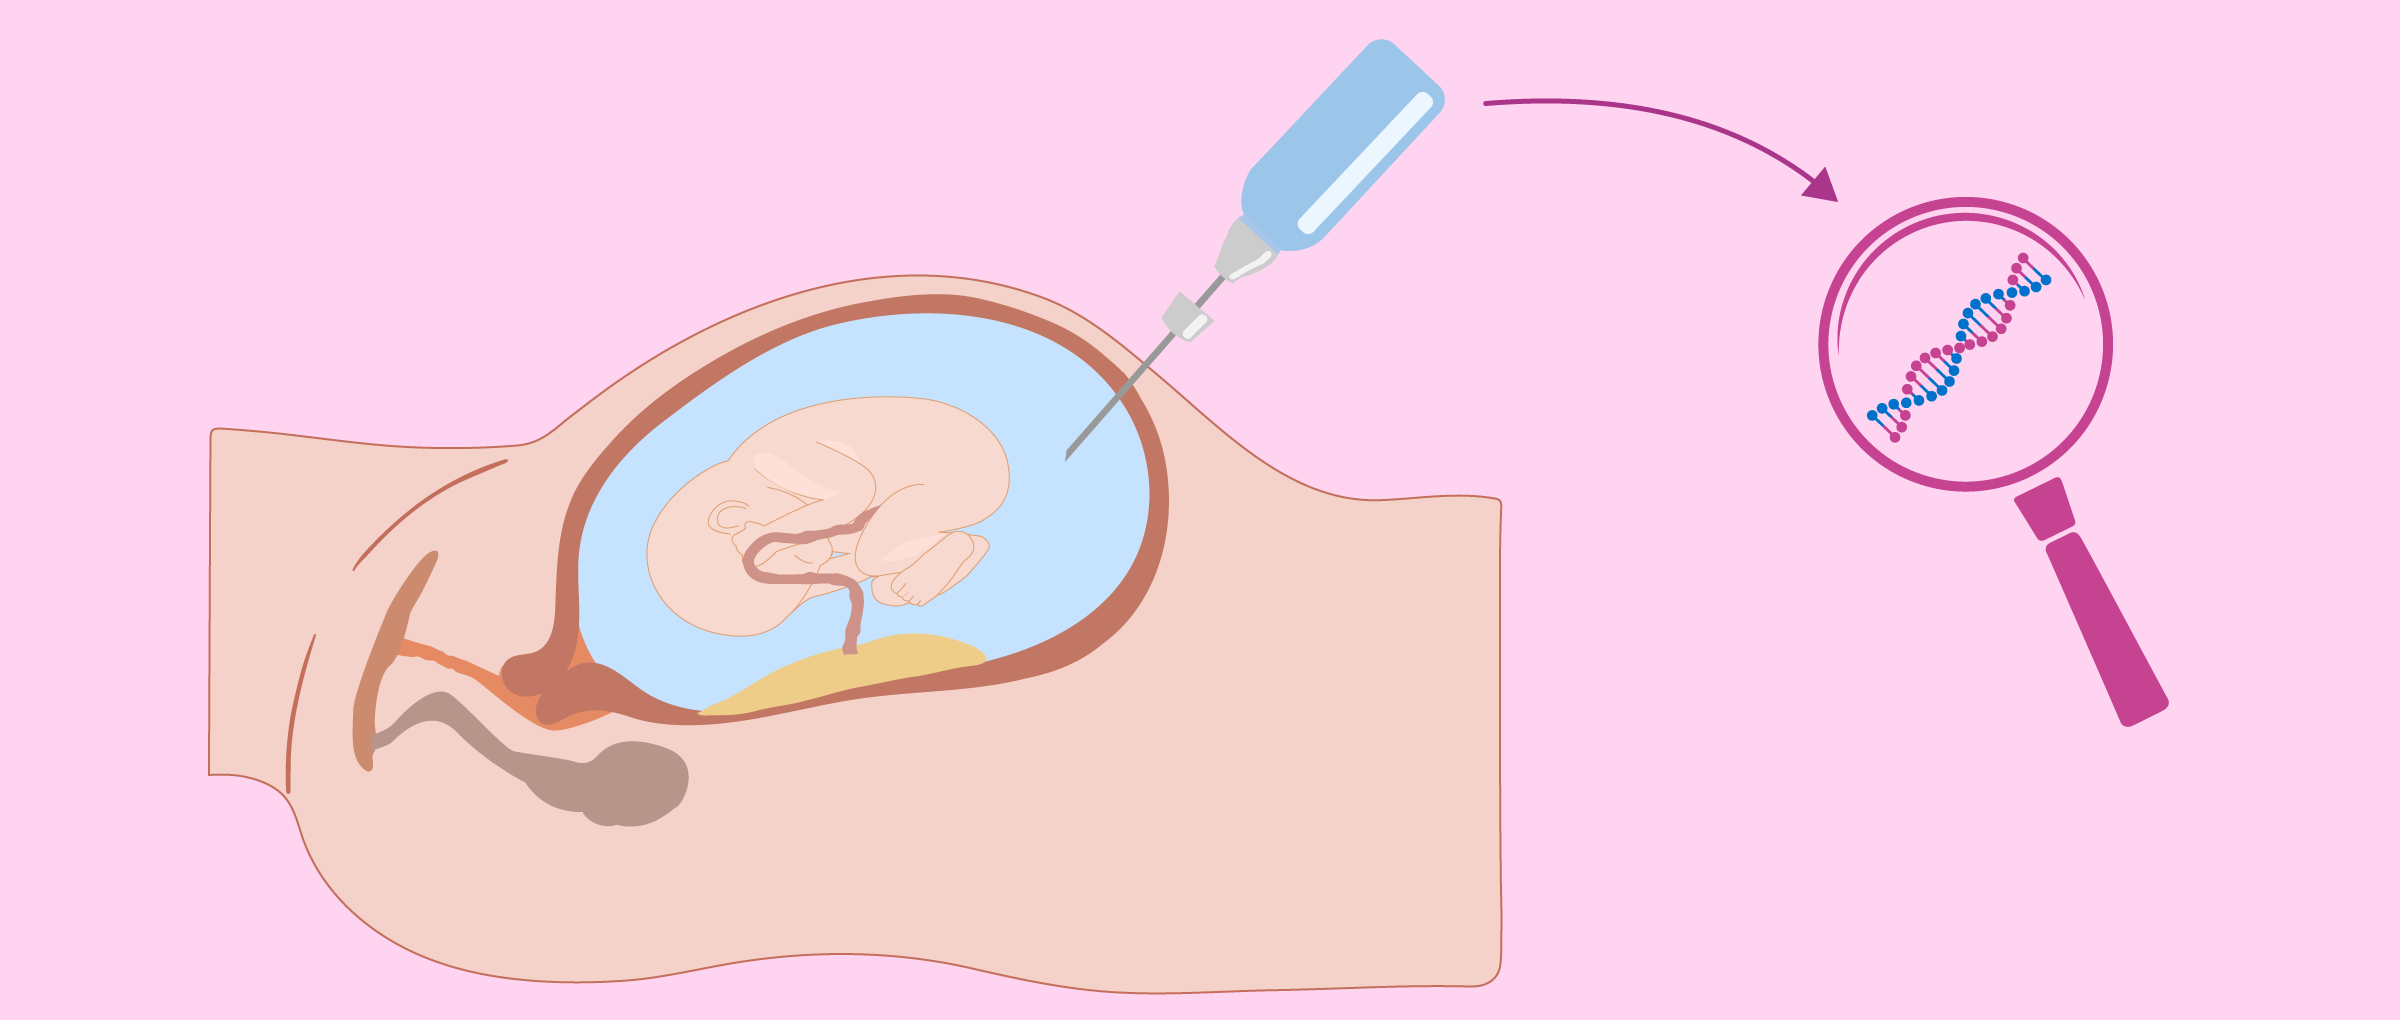

羊膜穿刺术和绒毛膜活检(也称为绒毛膜绒毛样本或 CVS)可以诊断染色体异常和出生缺陷。例如,他们会让我们知道婴儿是否患有唐氏综合症。

·羊膜穿刺术- 在 16 至 20 周期间取出羊水样本进行分析

·绒毛膜活检- 去除一块绒毛膜(覆盖胚胎的外鞘)。它在第 10 周和第 12 周之间进行

羊膜穿刺术和绒毛膜活检都是侵入性检查,当孕妇怀有多个孩子时,这些检查会变得更加微妙。应从每个婴儿身上采集样本,不要混淆他们。对于三胞胎或更多婴儿,您并不总是能得到他们。

此外,在多胎妊娠的情况下,与这些测试相关的风险会增加。羊膜穿刺术后流产率增加五倍,绒毛膜活检后流产率增加四倍。

借助植入前遗传诊断 (PGD) 程序,可以从胚胎中提取一种或多种细胞,以分析其遗传物质。通过这种方式,可以排除染色体改变,并增加移植合适胚胎的机会。因此,越来越多的人建议移植单个胚胎以避免双胞胎妊娠,同时又不会降低成功的机会。

怀孕期间,羊膜穿刺术和绒毛膜活检等侵入性检查可以提供可靠的诊断,但风险总是很小。因此,低风险孕妇不强制进行基因检测。